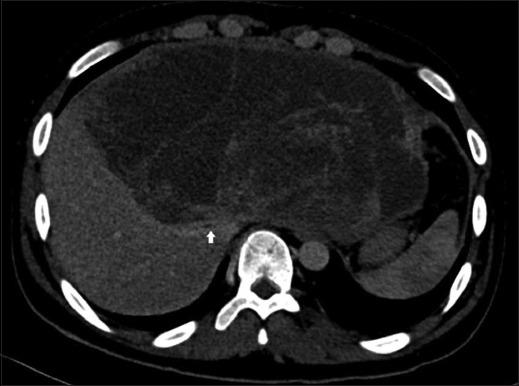

A 20-year-old boy with a large palpable abdominal mass, shortness of breath, and weight loss presented to our clinic. His computed tomography scan showed showed a large cystic lesion measuring 11.5 × 22.7 × 23 cm, predominantly involving the left lobe and right anterior sector, with a biopsy consistent with UESL. The tumor was abutting to the right hepatic vein, with bland main portal vein thrombosis. Due to an irresectable tumor and deteriorating clinical condition, living donor LT was performed. The patient remains in good health at 16 months of follow-up.

一名20岁男孩因可触及的腹部肿块、呼吸急促和体重减轻前来我院就诊。他的计算机断层扫描显示一个11.5×22.7×23厘米的大囊性病变,主要累及左叶和右前叶,活检结果与UESL一致。肿瘤紧邻右肝静脉,主门静脉有非血栓性病变。由于肿瘤无法切除且临床状况恶化,进行了活体供体肝移植。随访16个月时,患者健康状况良好。